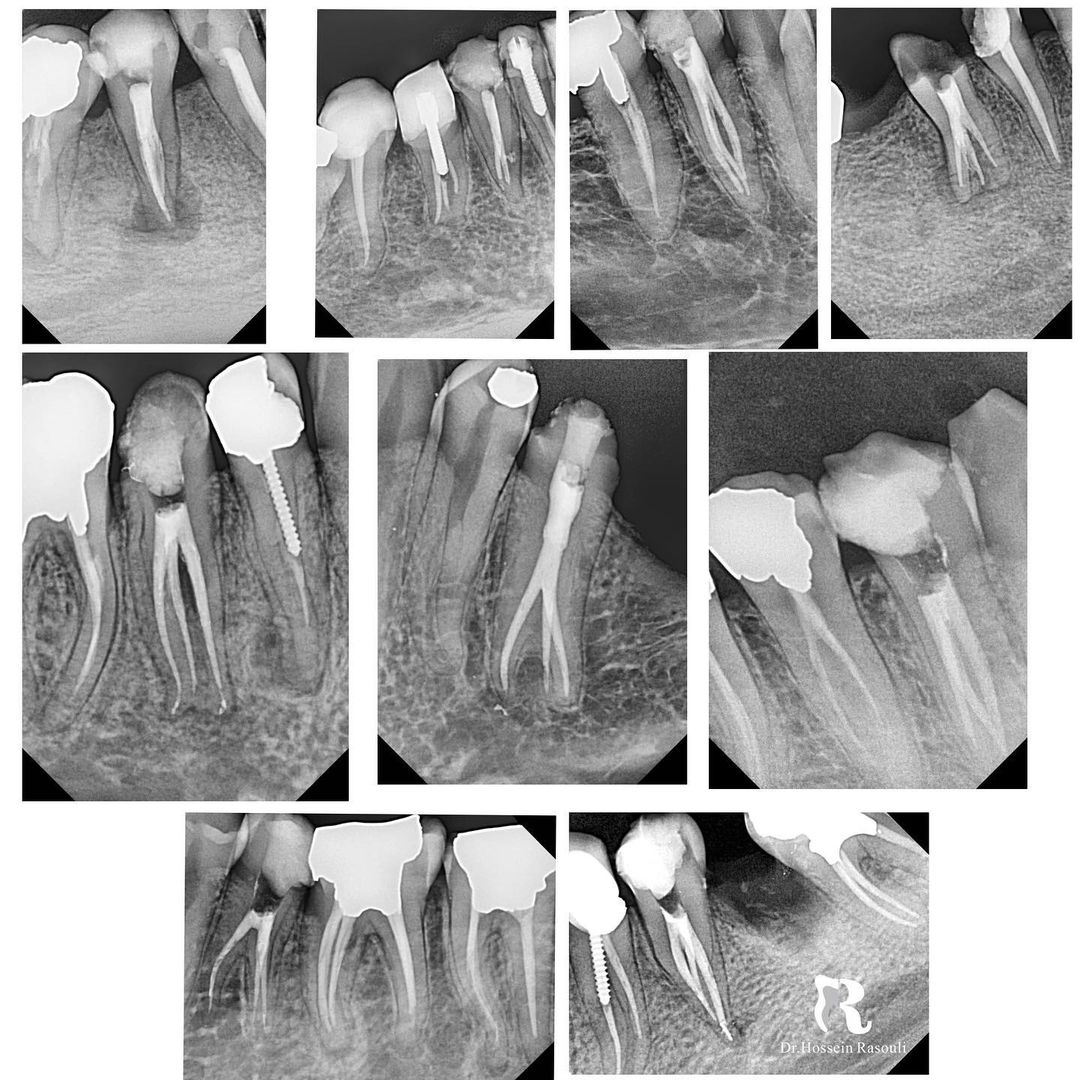

Collection of 3-canal lower premolar.

Collection of 3-canal lower premolar.